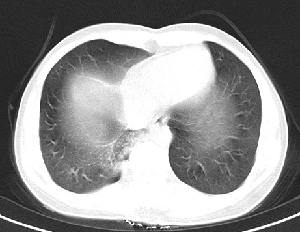

下叶后基底段近膈面见一椭圆形密度均匀增高的阴影,边界较清,其长轴指向内后方,考虑肺隔离症,建议增强扫描了解与主a联系!

1\\没有什么病史吗,没有看到与腹主动脉有联系呀,肺隔离症不是太象

肺血管畸形也有可能。

1.后纵隔神经原肿瘤,2.炎性假瘤。建议密切结合临床或抗炎治疗后复查。